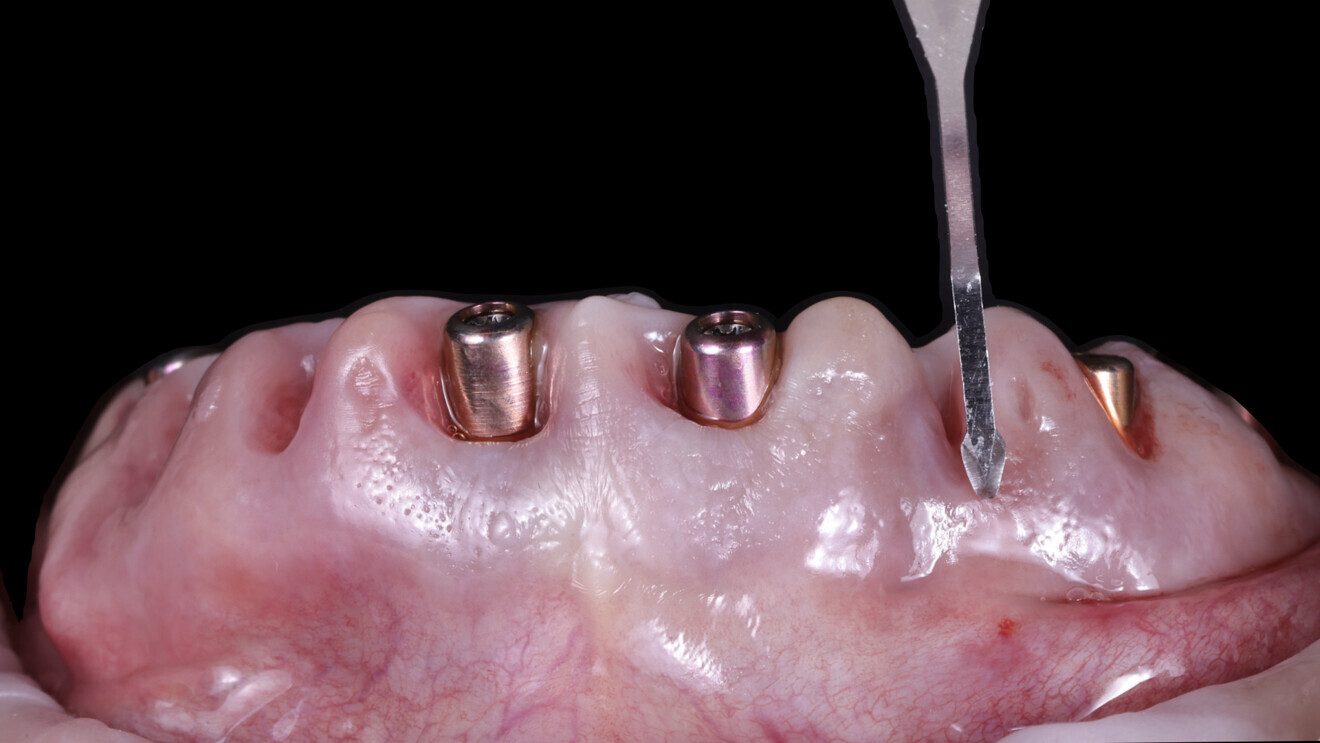

4. Guided implant placement: Eight implants were placed using a guided approach, achieving optimal progressive torque of 35 N cm and excellent bone–implant contact (Fig. 17).

5. Multi-unit abutment seating: The multi-unit abutments were torqued to 25 N cm.

6. Placement of SmartFlag scan bodies: The scan bodies were attached. The remaining teeth served as reference points for the dental technician to align the digital impression with the preplanned design and fabricate the temporary restoration.

7. Final tooth extractions: The remaining teeth were extracted to ensure a clean surgical site, and healing abutments were placed on the implants (Fig. 18).